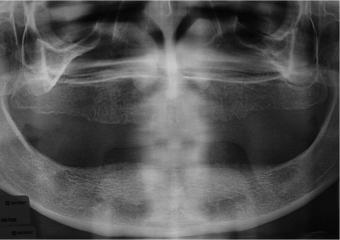

Raio X inicial - Clínica Cliniface

Raio X inicial